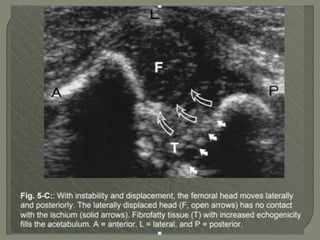

Ultrasound 1]More reliable inrevealing a joint effusion in early cases. Widening of space between capsule and bone of > 2mm indicates effusion. 2]Echo-free - transient synovitis 3]Positively echogenic septic arthritis

Oblique sagittal ultrasoundof the hip of a 17-month-old child with septic arthritis shows an echogenic effusion and synovitis